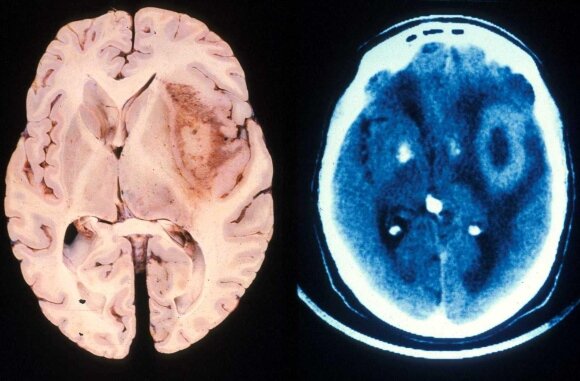

Глиома (глиобластома) – очень быстро прогрессирующая и часто смертельная опухоль головного мозга, при которой терапия имела какой-либо положительный эффект всего дважды за последние 30 лет. Но, кажется, появилась надежда. Согласно статье, опубликованной на днях в Cancer Research, исследователи, во-первых, обнаружили биомаркёр фермента, напрямую связанного с агрессивностью глиомы, во-вторых, открыли механизм регулирования этого фермента и, в-третьих, разработали для него вещество-ингибитор (подавляет активность), которое показало большую эффективность в попытках вылечить мышиную модель глиомы. Вещество GA11 имеет структуру, которая напоминает естественный ингибитор фермента-агрессора, но чуть изменённую, настолько, чтобы оно могло пройти сквозь гематоэнцефалический барьер. «Обе эти особенности делают GA11 привлекательным кандидатом в лекарства против глиомных стволовых клеток в мультиформной глиобластоме – крайне злокачесвенном типе опухолей головного мозга», — отмечает Ичиро Накано (I

Мультиформная глиобластома (Glioblastoma multiforme, GBM) – очень грозное злокачественное новообразование. Согласно данным последних 30 лет, выявлено лишь два случая, когда средняя выживаемость пациентов составила от пяти до 15 или 16 месяцев, а, в основном, больные умирают очень рано.